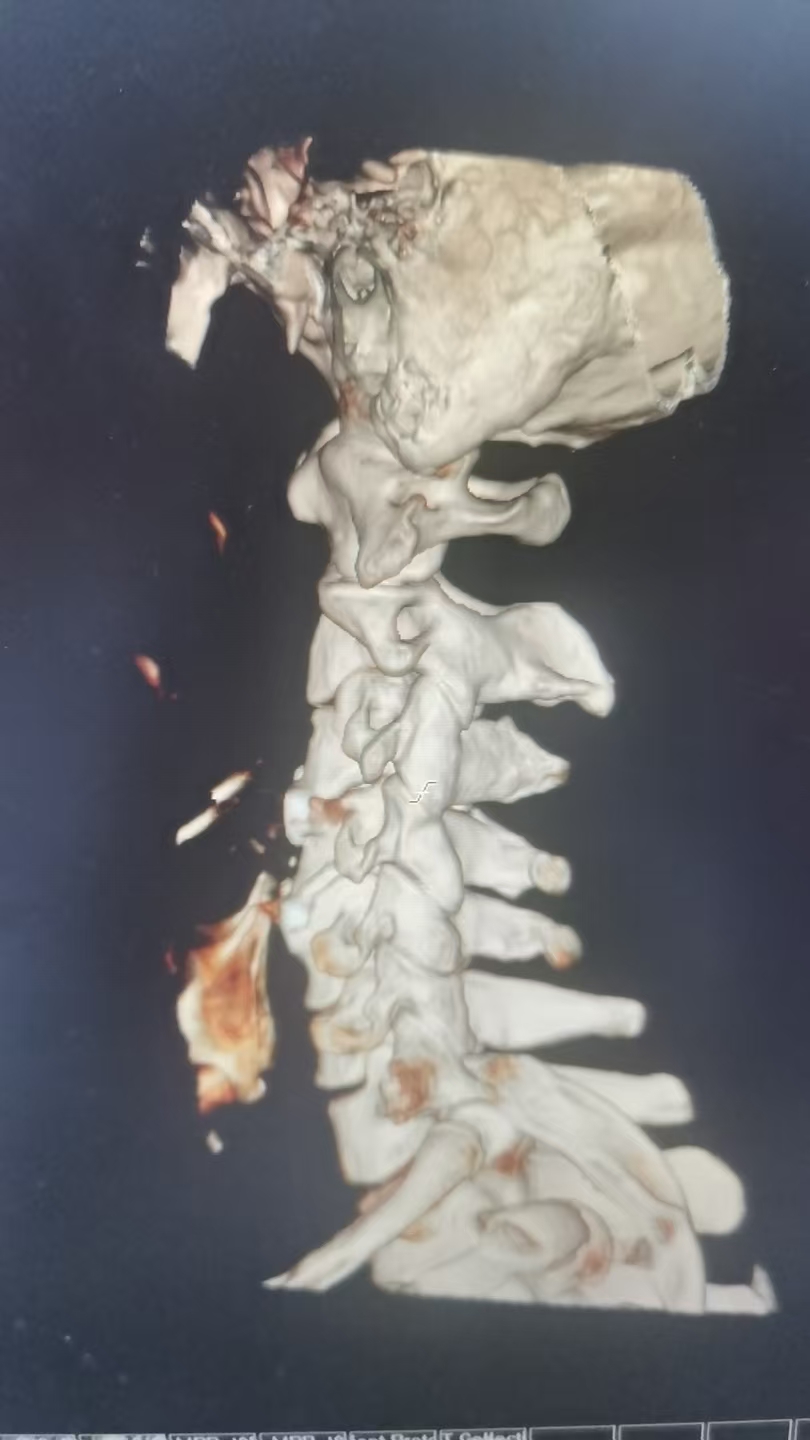

47岁李先生(化名)近日因车祸导致“颈髓损伤,四肢麻木无力”入院。经我院脊柱外科团队详细检查,影像学检查显示颈3/4及4/5节段椎间盘突出,脊髓神经根受压,引发四肢不完全瘫痪。术前右侧上、下肢体肌力:3级,左上肢肌力3级,左下肢肌力1级。

由于保守治疗效果不明显,医护团队综合评估后,决定为患者施行颈椎前路微创手术。在南医三院派驻骨科专家、东凤人民医院副院长闫慧博(挂职)的带领下,我院骨科团队共同为患者实施“颈椎3/4、4/5双节段前路椎间盘摘除+椎体融合术”。

手术过程:一次精准的“椎间修缮”

✅ 微创入路:在颈部前方沿皮纹作一约2–3厘米小切口,避开重要血管与组织,精准抵达病变颈椎。

✅ 彻底减压:摘除突出椎间盘,解除对神经和脊髓的压迫。

✅ 稳定融合:植入高度与曲度精确设计的椎间融合器,填充人工骨材料,重建椎间隙高度与曲度,促进椎体间长期稳定融合。

(术中图)